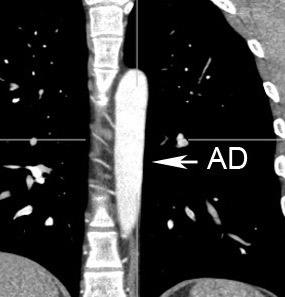

“Draped aorta”.

Indica rotura aórtica reciente. Se manifiesta por una pared aórtica posterior o el contacto con el borde lateral vertebral borrados por la hemorragia.

A. Yudin, Metaphorical

Rotura aneurisma de Aorta descendente.

Dolor. (10 días antes: "Rotura inminente”)